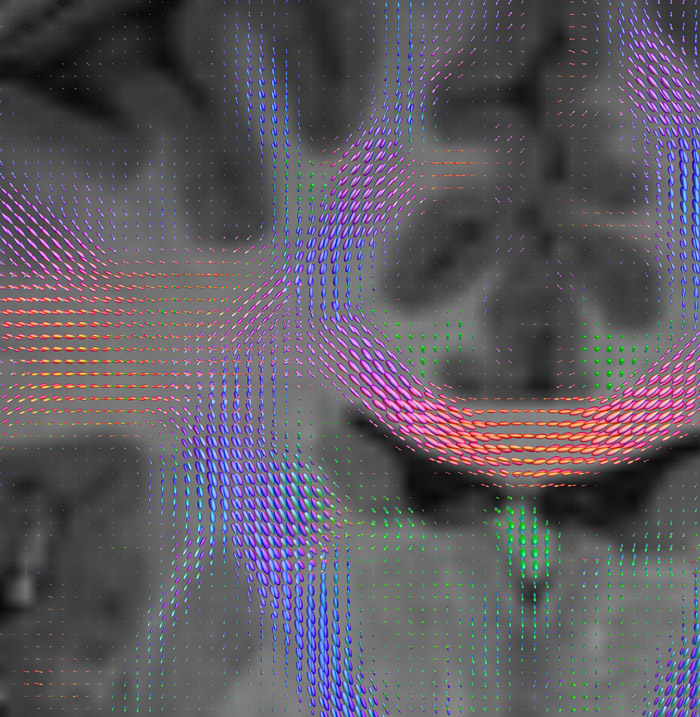

Fiber orientation density

CSD of multishell DWI results in the white matter FOD at each voxel. Unlike the conventional diffusion tensor model, this approach enables accurate modeling of multiple fiber populations within a single voxel.

Crossings of the corpus callosum, corticospinal tracts, and the superior longitudinal fasciculus are shown.